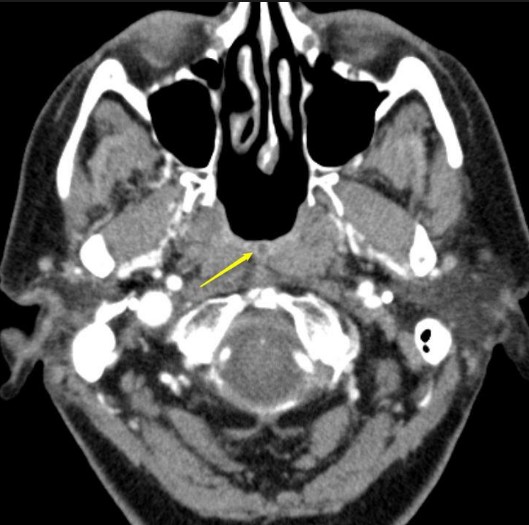

КТ мягких тканей шеиБлагодаря КТ можно оценить анатомию органов шеи, их структурные аномалии и особенности взаимного расположения. На снимках КТ шеи визуализируются трахея, глотка, гортань, щитовидная железа, клеточные пространства, паращитовидная железа, слюнные железы, сосуды, костные ткани, лимфоузлы и мышечные волокна.

КТ мягких тканей шеи позволяет оценить распространенность патологии в клетчаточных пространствах данной области, применяется для изучения состояния лимфоузлов, степени инвазии крупных сосудов шеи опухолью смежных тканей.

Данный протокол сканирования используется для выявления воспалительных, опухолевых и посттравматических изменений. КТ является приоритетным способом лучевой диагностики рака горла и гортани, оценке размера злокачественного образования, стадии, вовлеченности в процесс других тканей. Исследование также показывает отек или стеноз гортани, аномалии ее развития, наличие инородных тел в горле или гортани, сдавление пищевода, причины нарушения актов глотания и пр.

КТ горла и мягких тканей шеи во многих случаях рекомендуется проводить с контрастным усилением из-за близких плотностных показателей тканей данной области и тесного расположения структур.

Компьютерная томография шеи с контрастированием обязательно применяется для поиска и дифференцирования объемных образований, а также сосудистых нарушений.